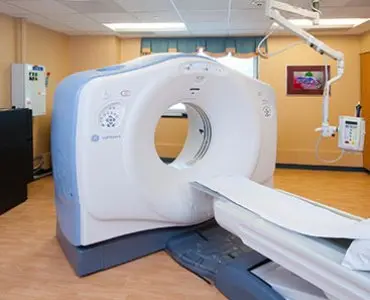

Our Services

We are a large team of radiologists working either on specific modalities

or specialize in organ specific imaging.